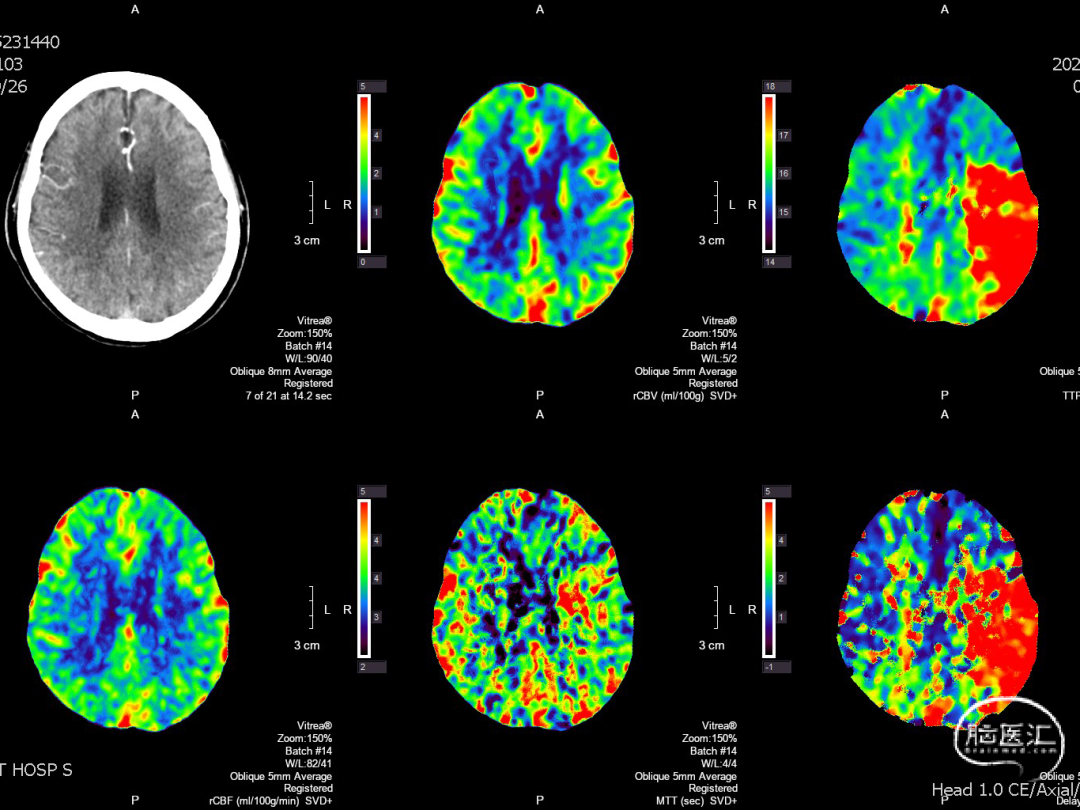

术前CTP

复查CT及CTP:未见出血及低灌注区。